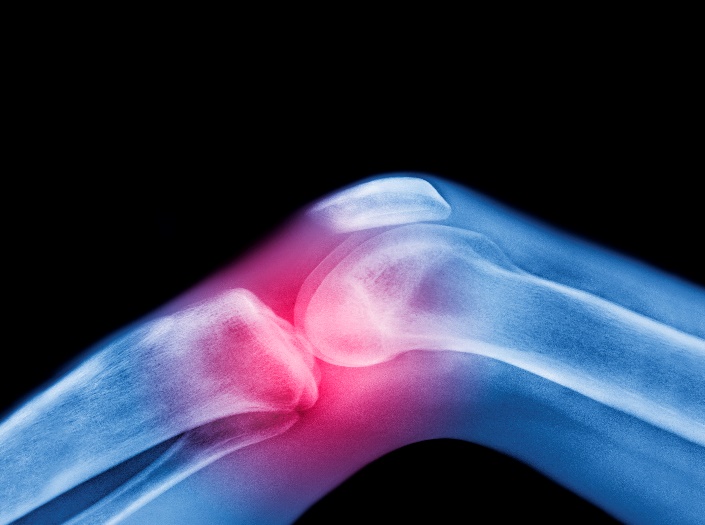

注重骨密度檢測 防治骨折發生

據統計,國內每年因骨質疏鬆症造成的骨折高達 13 萬人次,其中有 3000~5000 人因股骨骨折引起併發症而死亡。醫師提醒,民眾需要提高骨鬆的認知,注重骨密度檢測與避免跌倒,以「預防勝於治療」共同防治骨折發生。